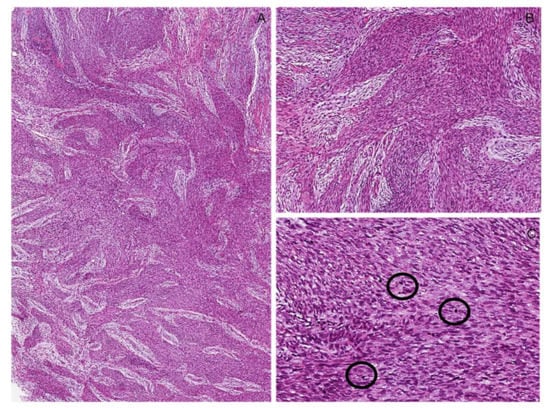

6.3. Cellular Schwannoma

Immunohistochemical Features